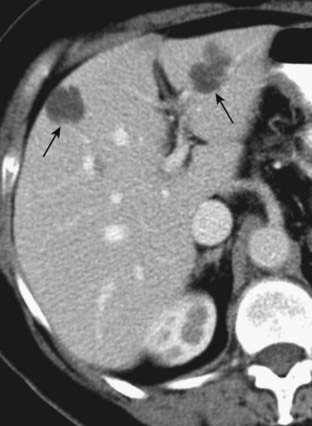

image

Figure 18-31 Metastases to the liver and spleen.

Metastases usually appear as multiple, low-attenuation masses (solid black arrows). There are also low-attenuation lesions in the spleen (dotted black arrow). The patient had a primary adenocarcinoma of the colon.